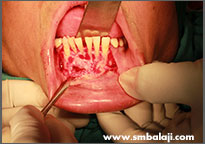

X-ray showing teeth impacted in the lower right jaw region

Impacted teeth surgically removed